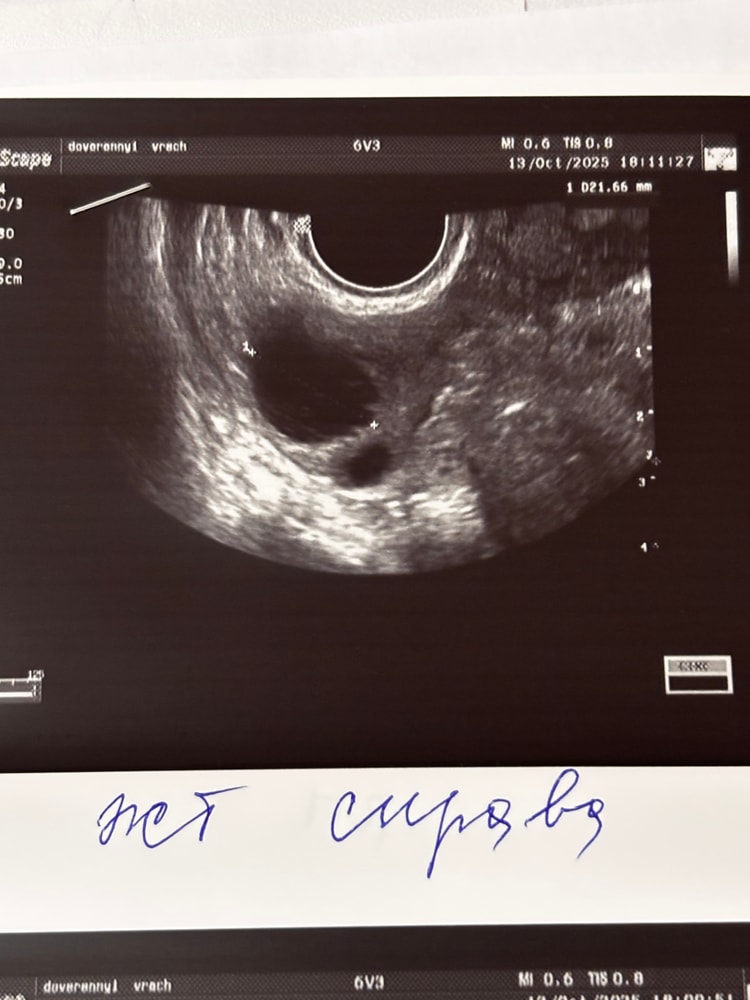

Li → Зачатие УЗИ Нижний Новгород ЖЕЛТОЕ ТЕЛО на УЗИ, ДОМИНАНТНЫЙ ФОЛЛИКУЛ на УЗИ Девочки, подскажите пожалуйста, как выглядит на УЗИ ДФ И ЖТ, может у кого есть фото. Спасибо 🙌 Посмотрите еще 20 записей на эту тему Лучший ответ Лера Мама девочки (11 дней) Москва Жт 0 13.11.2025 Ответить Li Нижний Новгород Лера, спасибо большое 0 13.11.2025 Ответить Лера Мама девочки (11 дней) Москва Дф 0 13.11.2025 Ответить Помогите разобраться какой дпо Пя 5,8 на 6.1 неделе Похожие записи 4 доминантных фолликула на клостике!!! Нет доминантного фолликула, эндометрий 5.3. ЖТ и доминантный фолликул 2 Протокол и доминантный фолликул 13 мм на старте Желтая моча у младенца Чаты Беременных Выберите чат: Июлята-2026 Августята-2026 Сентябрята-2026 Октябрята-2026 Ноябрята-2026 Декабрята-2026